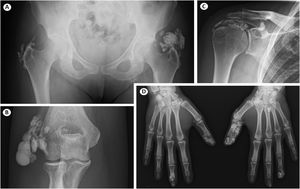

During the 12 years of follow-up, the most prominent complaints were related to the function limitation caused by calcinosis cutis. She also developed exuberant widespread calcinosis in other fingers, right elbow, right shoulder and hips. Several therapies were tried, including bisphosphonates, diltiazem, colchicine, minocycline and intravenous immunoglobulin, without any benefit. Three surgeries on the 1st and 3rd fingers of her right hand were performed to excise calcium deposits; despite that, calcinosis returned at the same locations. Current radiographic images show the ineffectiveness of treating calcinosis cutis (Fig. 1).